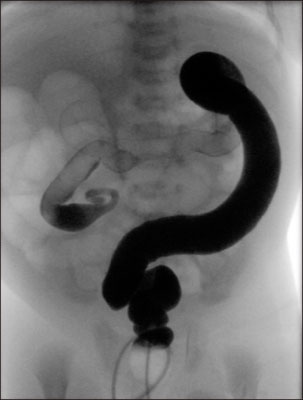

Full-term 52-day-old boy with total colonic aganglionosis. False-positive transition zone (arrow) is noted at the descending colon (case 3).

Fig. 1 Full-term 52-day-old boy with total colonic aganglionosis. False-positive transition zone (arrow) is noted at the descending colon (case 3).